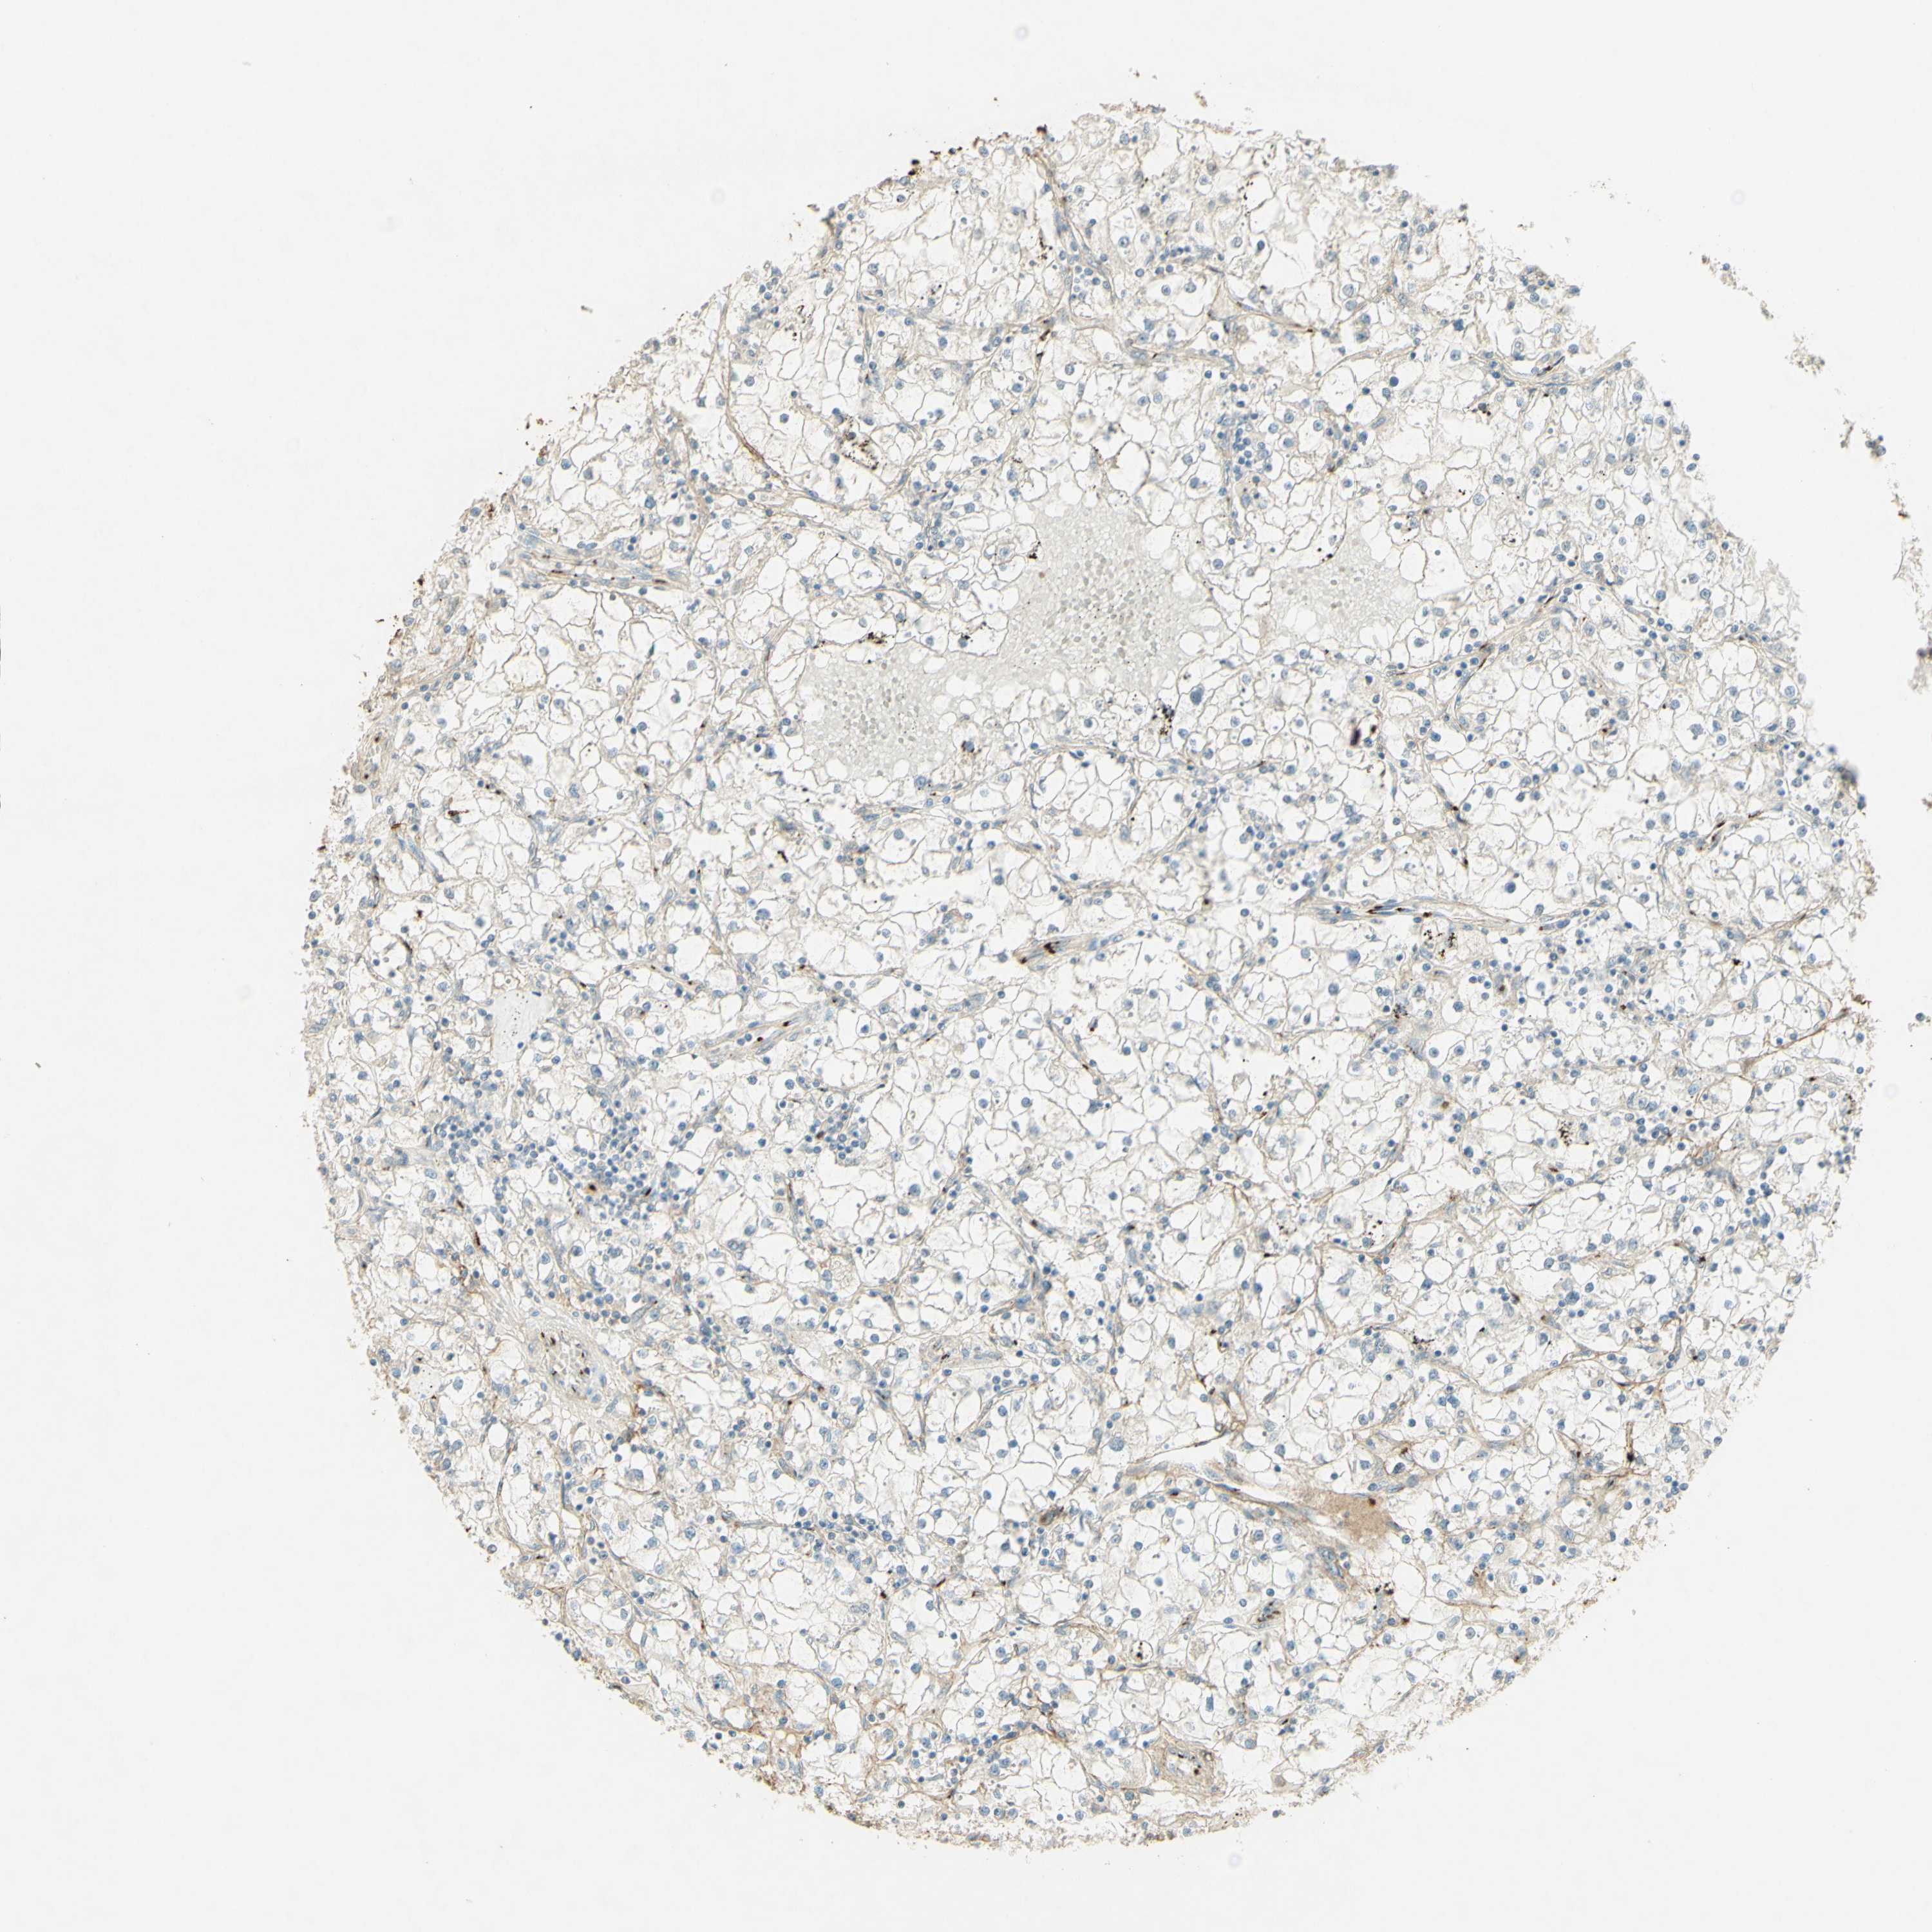

TCGA RNA samplesi

RNA-seq data is reported as average FPKM (number Fragments Per Kilobase of exon per Million reads), generated by the The Cancer Genome Atlas (TCGA) .

Normal distribution across the dataset is visualized with box plots, shown as median and 25th and 75th percentiles. Points are displayed as outliers if they are above or below 1.5 times the interquartile range. FPKM values of the individual samples are presented next to the box plot.

Average pTPM 0.5